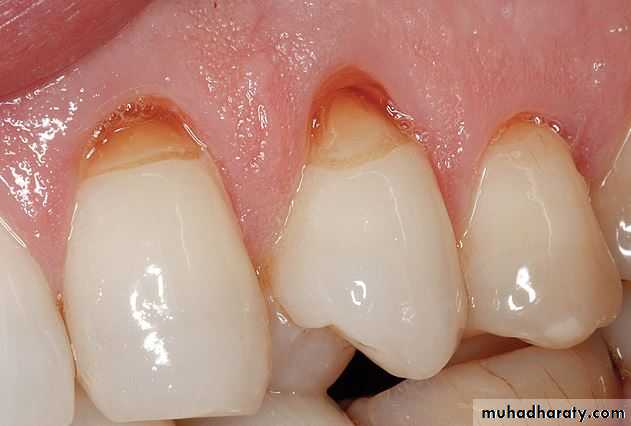

Causes: Causative factors include caries, exposed dentin, recent dental treatment, and defective restorations.

incipient caries.

cervical erosion and occlusal (incisal)attrition

Deep restorations, caries, pulp exposure, or any other direct or indirect insult to the pulp, recently or historically, may be present